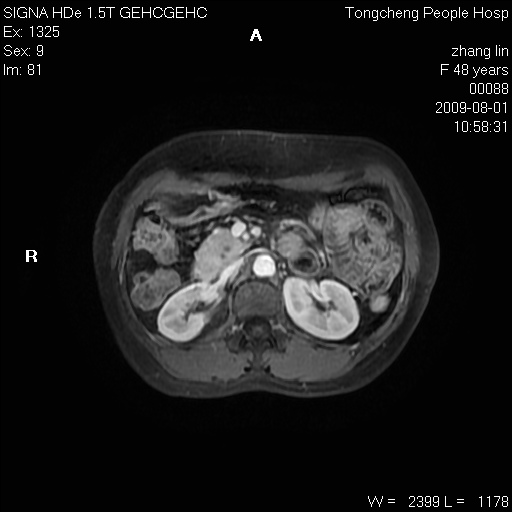

女,48岁。健康体检,彩超发现右肾占位性病变。平素健康。

临床诊断:右肾占位性病变,性质待定(囊肿?肿瘤?)。

上中腹部mr平扫+增强扫描,图像如下:

右肾上极见一类圆形病灶,t1wi呈等信号t2wi呈等高混杂信号,三期增强无强化,边界清---考虑囊肿出血。

同反相位均表现为等信号,病变无强化,考虑含蛋白的囊肿可能,弥散加权相或许有些帮助,

慢性胆囊炎